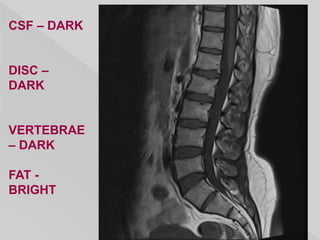

CSF – DARK

DISC –

DARK

VERTEBRAE

– DARK

FAT -

BRIGHT